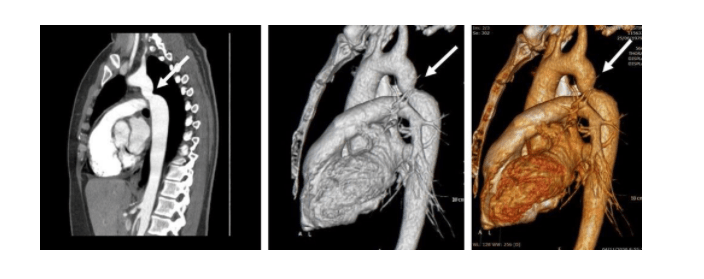

Η ασθενής διερευνήθηκε περαιτέρω με αξονική αγγειογραφία της αορτής για την επιβεβαίωση ή τον αποκλεισμό της διάγνωσης. Η εξέταση έδειξε ελίκωση και ήπια στένωση του αυλού της θωρακικής αορτής περιφερικά της αριστερής υποκλειδίου αρτηρίας (εικόνα – λευκά βέλη) και ήπια μεταστενωτική διάταση της κατιούσας θωρακικής αορτής, ευρήματα συμβατά με ψευδή στένωση του ισθμού της αορτής.